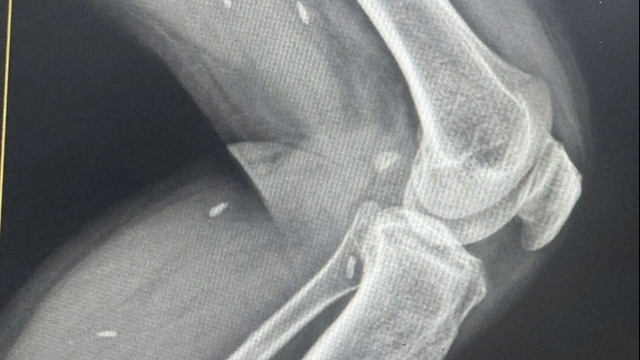

BN số 91 hiện là bệnh nhân nặng nhất, 2 phổi đông đặc, Hội đồng chuyên môn đang xem xét phương án ghép phổi.